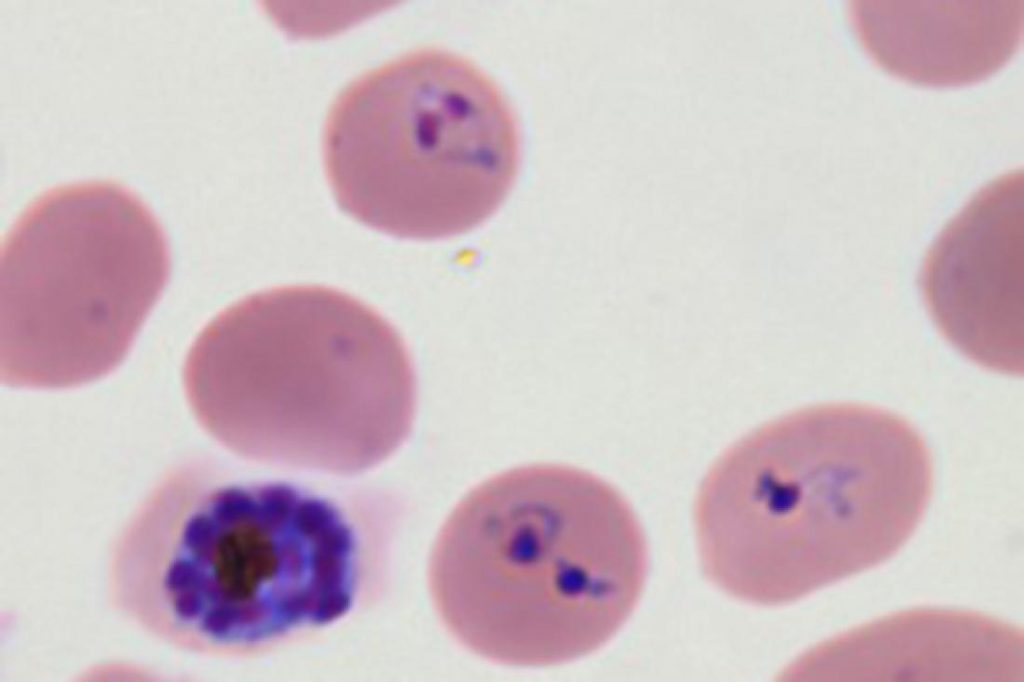

Malaria parasites transform healthy red blood cells into rigid versions of themselves that clump together, hindering the transportation of oxygen. The infectious disease affects more than 200 million people across the world and causes nearly half a million deaths every year, according to the World Health Organization’s 2018 report on malaria. Until now, however, researchers did not have a strong understanding of how the parasite so effectively infiltrated a system’s red blood cells.

The researchers focused on Plasmodium falciparum, the parasite that causes the most severe form of malaria. This parasite infects a host red blood cell, triggering the production of several proteins into the host cell’s cytoplasm—the bulk of the cell’s mechanics and the liquid in which they’re held, ultimately transforming the cell’s physical form. Not only does this transformation make the cells stick in place, out of the body’s immune response, it also helps the parasite travel to the surface of the cell and infect others. Together, the proteins work to proliferate the parasite, leading to the propagation of the malaria parasite.